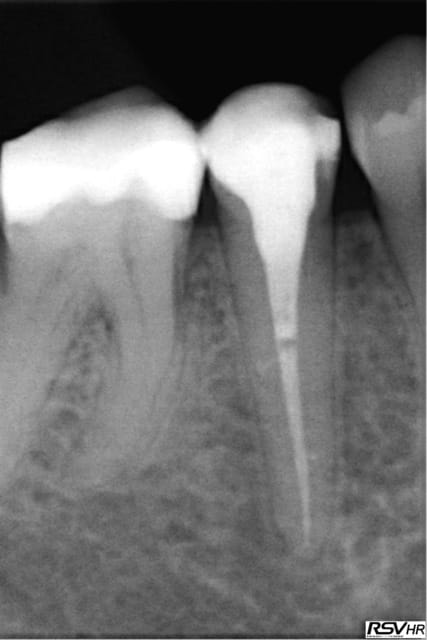

je joins un cas de traitement sur 45 ;nécrobiose,digue,hypo

1 instrument acier en cathétérisme,séquence NITI héroshaper

20%à6% puis4% 25à4% 30à4%,sealite regular,1 cône gutta fine-médium,1 compactage avec thermocompacteur(traitement

sous A.B car risques de douleurs par reprise bactérienne

Chances: des canaux secondaires obturés par le ciment

guérison de l'apex pas de douleurs pendant le compactage

cône de gutta avec "tug back" légère sensation d'échauffement

pas de douleurs post-opératoires

Un rêve....(sauf pas de HN;reconstitution SC33;sauvé par la CCM)!